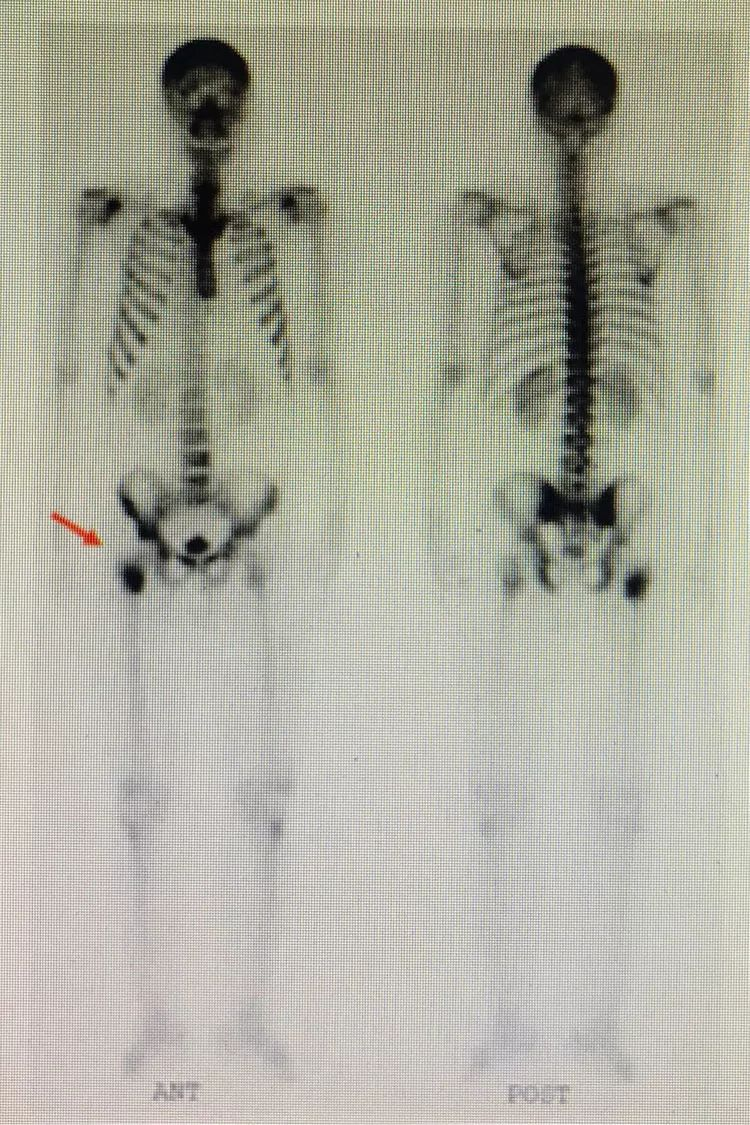

病例三:寻找肿瘤的原发病灶:骨肉瘤

男性,32岁,如图所示:红色箭头标志为可见患者右侧胫骨上段改变,考虑为恶性骨肿瘤。